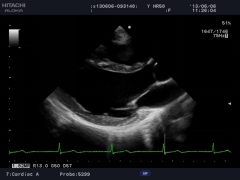

通過復(fù)合陣列探頭及SIP、AIP等多種成像技術(shù),為臨床帶來優(yōu)質(zhì)的二維圖像和敏感的血流,可以更加真實(shí)的反映血管的灌注情況,真實(shí)再現(xiàn)微細(xì)血管解剖形態(tài)。

作為原裝進(jìn)口的全身應(yīng)用型高檔全數(shù)字化彩色多普勒超聲診斷系統(tǒng),它在腹部、泌尿、婦產(chǎn)、乳腺、甲狀腺、淺表、腔內(nèi)、心臟等各個領(lǐng)域都有完美的圖像表現(xiàn)及豐富的應(yīng)用支持。